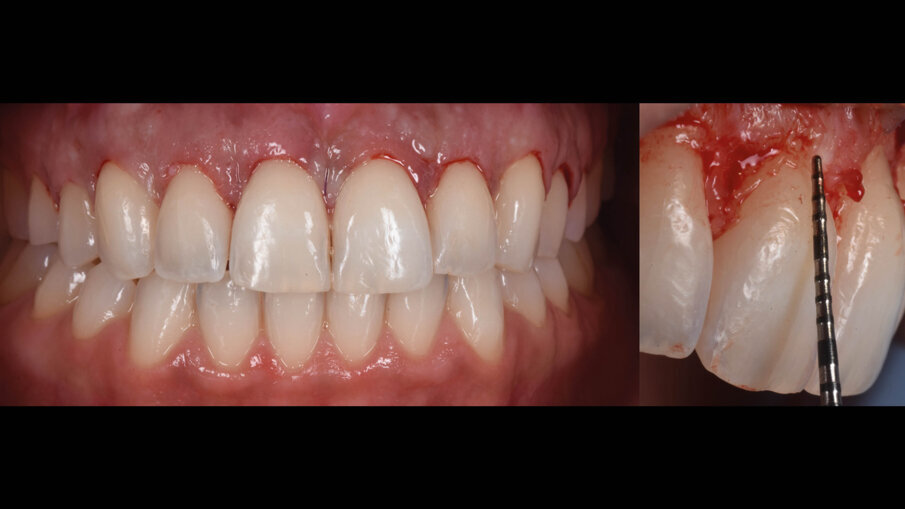

Una paziente di 25 anni si è presentata alla nostra attenzione per risolvere e migliorare il suo sorriso “gengivale”(Fig. 1). In prima visita lo status di rx endorali eseguite con il centratore di Rinn e la tecnica parallela confermavano la diagnosi di eruzione passiva alterata, la mancanza di “luce” negli spazi inter-prossimali e la posizione dei picchi ossei interprossimali rappresentano i segni caratteristici di questa problematica (Fig. 2). Lo studio del caso veniva completato eseguendo le fotografie, intra ed extra orali, la scannerizzazione delle arcate con uno scanner intra-orale e l’esecuzione della CBCT dell’arcata superiore (Fig. 3).

Fig. 1_Situazione iniziale.

È perciò possibile durante la procedura di allungamento di corona clinica eseguire foto e video con un paziente completamente cooperativo. La prima procedura è la gengivectomia che ha lo scopo di eliminare la gengiva in eccesso e di esporre lo smalto dei denti altresì nascosto (Fig. 12). Una volta completata questa procedura si procede all’elevazione di un lembo a tutto spessore vestibolare che si estende per tutta la zona interessata dalla procedura. La mascherina chirurgica viene a questo punto ri-inserita in bocca per poter assistere la resezione della quantità di osso indicata per correggere la dimensione della zona di attacco sopra crestale (Fig. 13) La chirurgia ossea resettiva viene eseguita con l’ausilio di frese diamantate a palla con diverse dimensioni per le zone vestibolari e interprossimali oppure con strumenti piezo-elettrici. A procedura ultimata si può vedere come la nuova anatomia sia più consona all’attacco dei tessuti molli e favorente una miglior salute dell’attacco dento parodontale (Fig. 14).

Fig. 12_Esposizione dello smalto dopo la gengivectomia.